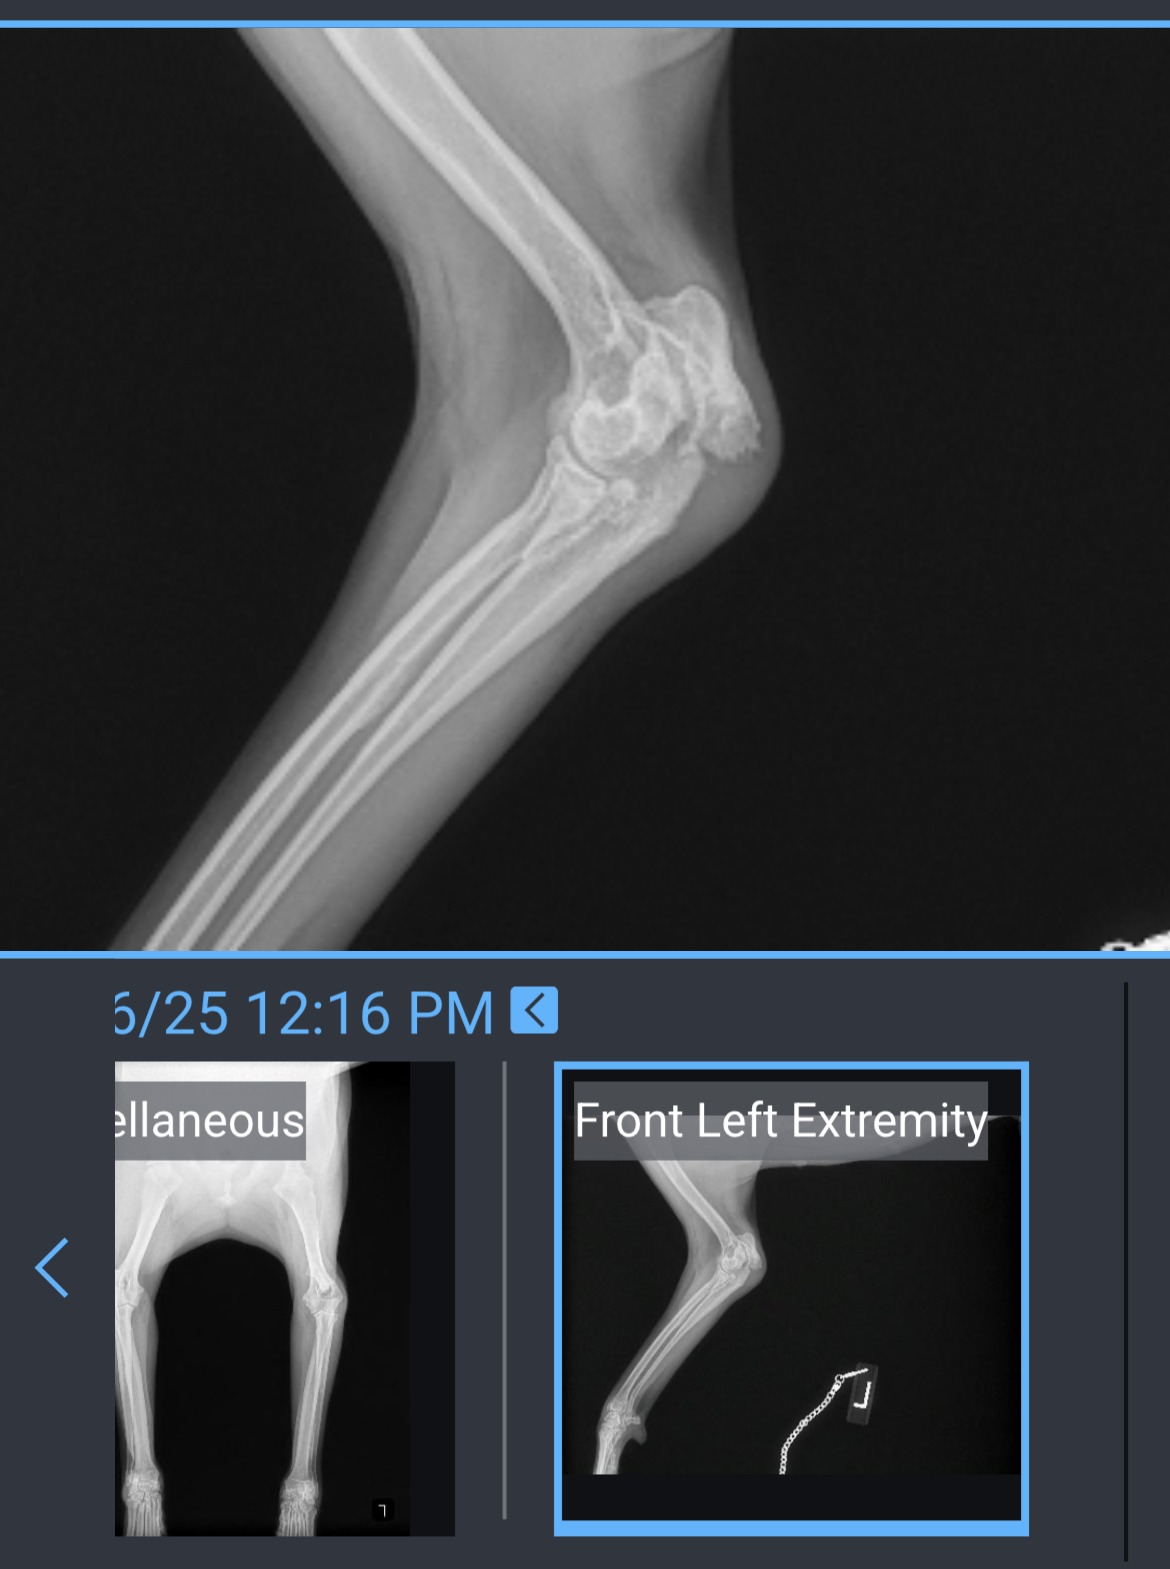

Sugar #A2698354 has been through more than any dog should ever have to endure. She arrived at the shelter on June 6, 2025 with a painful coronoid fracture in her elbow, leaving her unable to walk or bear any weight on her left front leg. While in the shelter’s care, she was also spayed while pregnant, a heartbreaking ordeal for any animal.

Since then, Sugar has been evaluated by two independent veterinarians, both of whom believe her leg can be saved with surgery.Now, we need your help to make that possible.